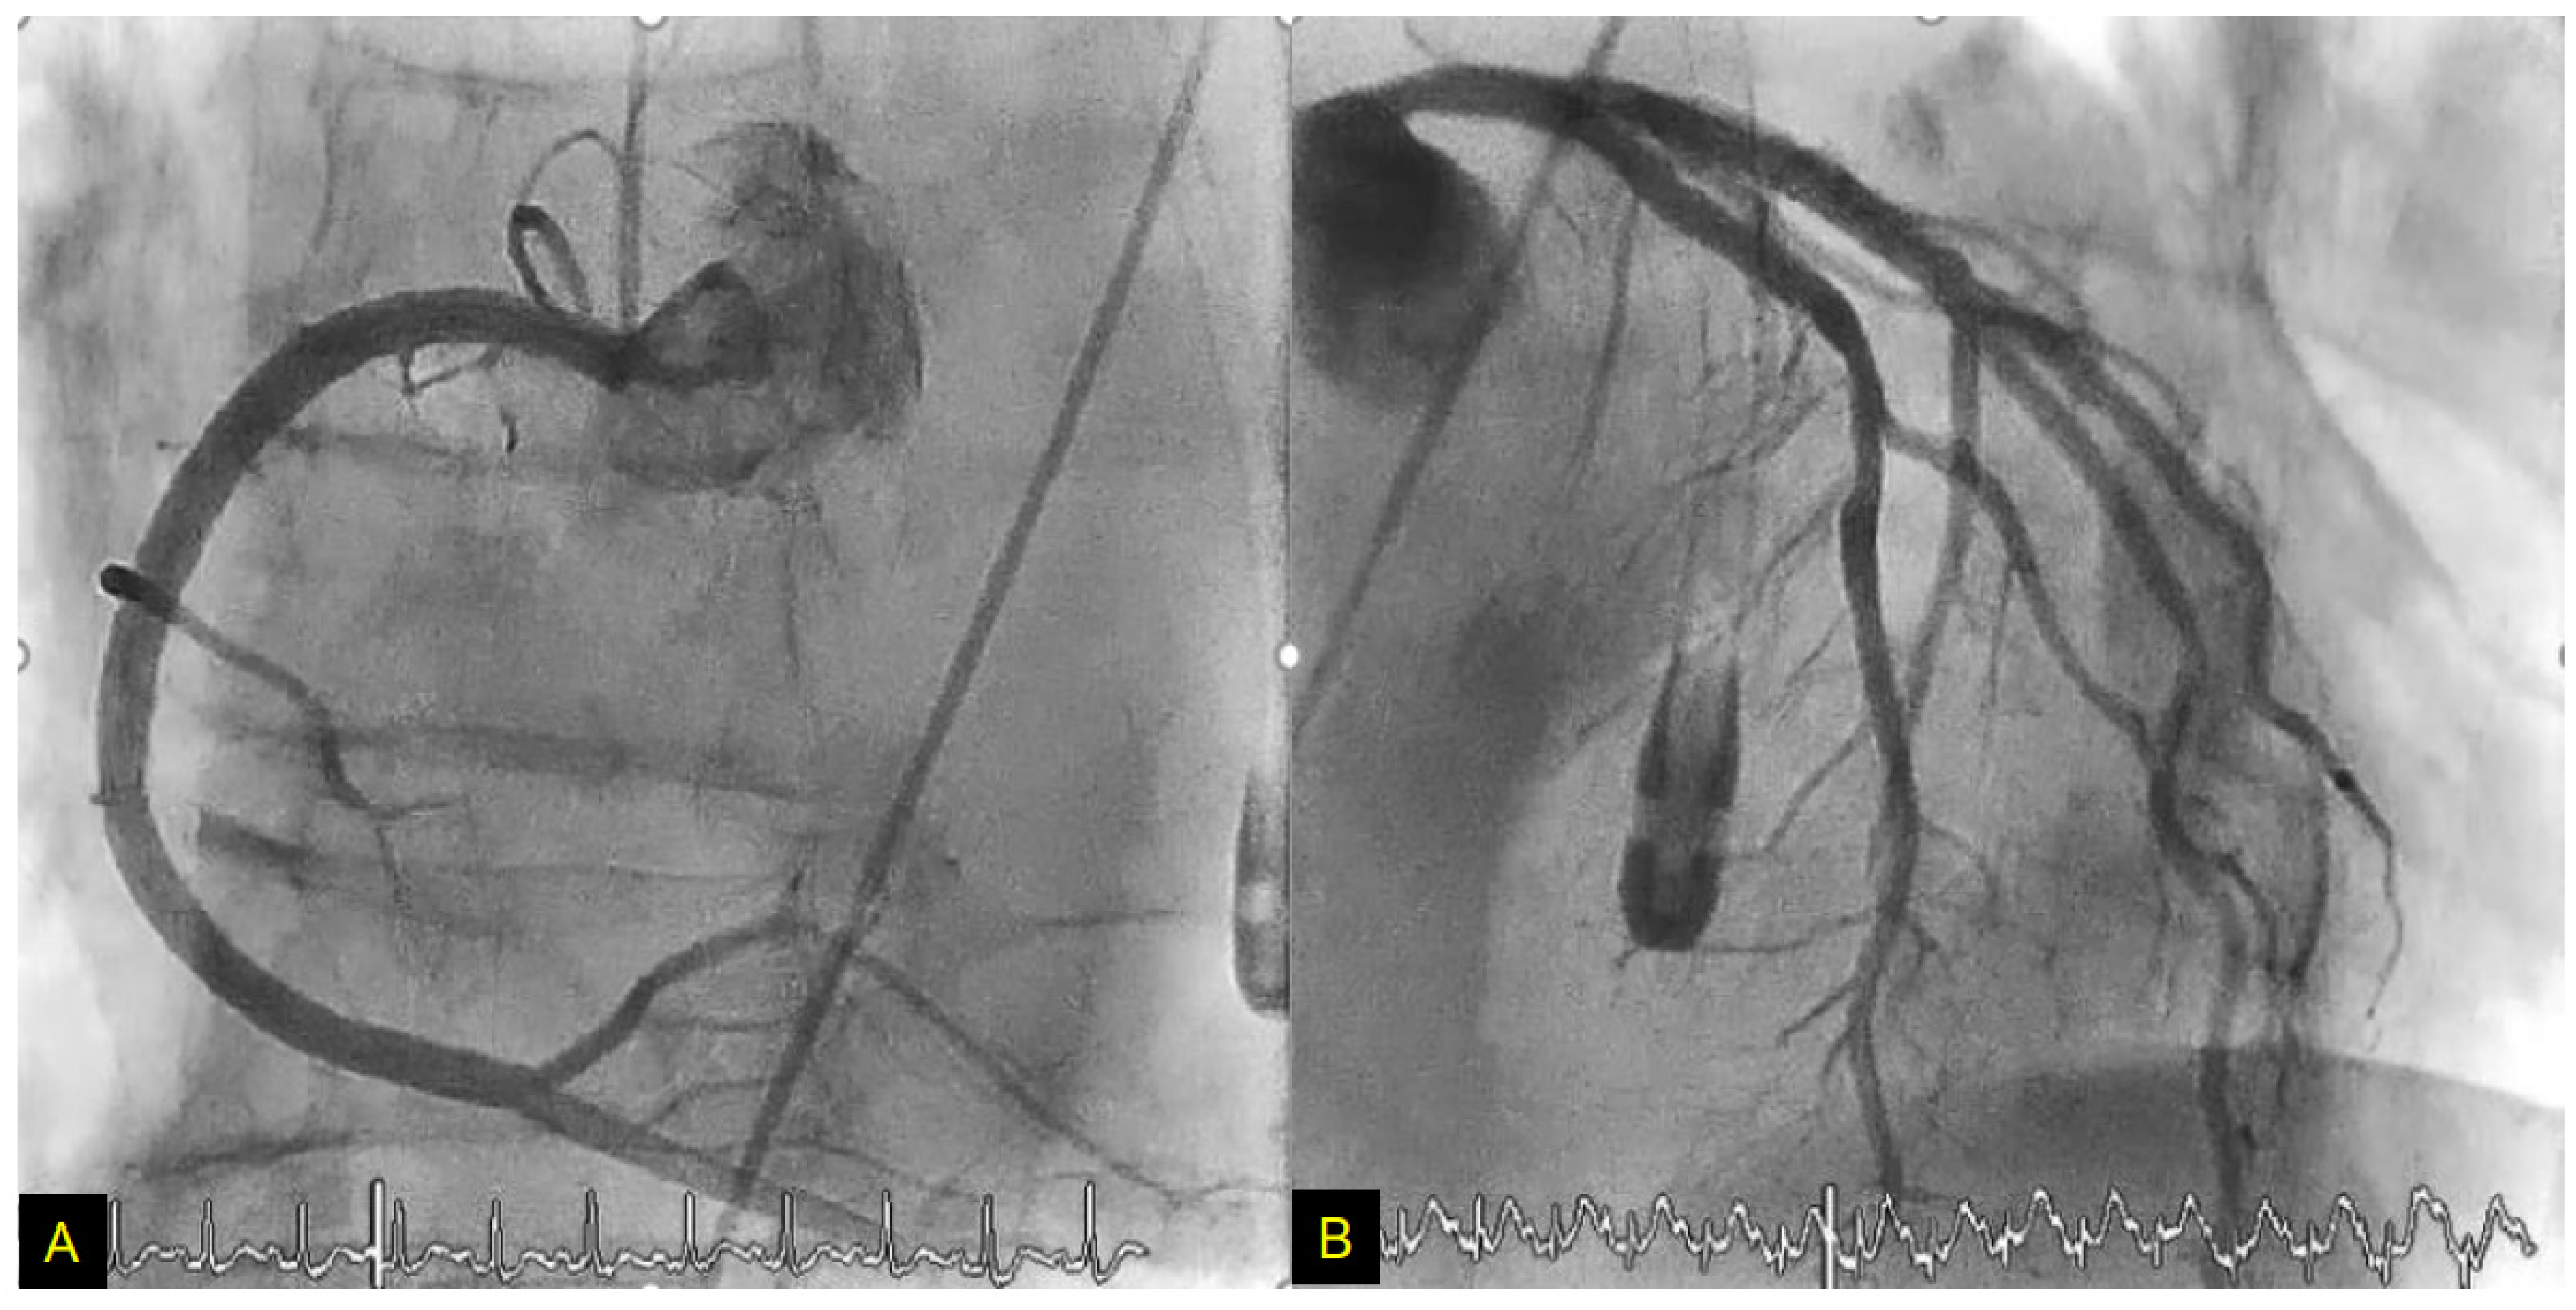

- Nagai, M.; Kobayashi, Y.; Kobatake, H.; Dote, K.; Kato, M.; Oda, N.; Kunita, E.; Kagawa, E.; Yamane, A.; Osawa, A.; et al. Happy heart syndrome: A case of Takotsubo syndrome with left internal carotid artery occlusion. Clin. Auton. Res. 2020, 30, 347–350. [Google Scholar] [CrossRef]

- Osawa, A.; Nagai, M.; Dote, K.; Kato, M.; Oda, N.; Kunita, E.; Kagawa, E.; Yamane, A.; Kobatake, H.; Shiota, H.; et al. A mid-ventricular variant of Takotsubo syndrome: Was it triggered by insular cortex damage? ESC Heart Fail. 2021, 8, 3408–3412. [Google Scholar] [CrossRef]